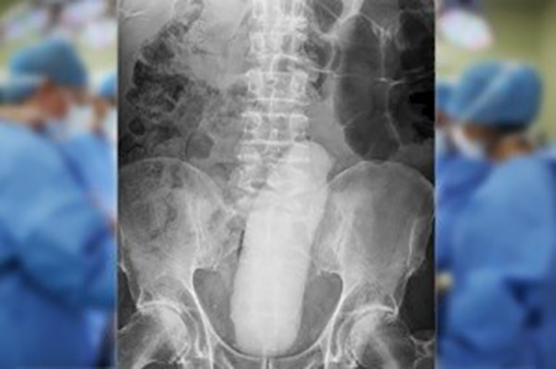

Idoso vai parar no hospital após ficar com vibrador de 23 cm preso no reto

Um aposentado de 68 anos foi levado às pressas para um hospital em Dublin na Irlanda. O homem teve que recorrer um cirurgia para retirar um objeto fálico de 23 cm de dentro anûs. Ele foi ao hospital após passar 10 horas tentando retirar o objeto em casa, mas começou a passar muito mal e precisou de ajuda profissional. Ele precisou ser anestesiado para que o objeto fosse retirado com uma pinça.

O evento inusitado aconteceu no Hospital Mater, na Irlanda, que comentou em seu relatório hospitalar.

“Um homem de 68 anos se apresentou ao setor de emergência com um grave desconforto abdominal inferior, distensão e incapacidade de urinar. Ele tinha inserido um objeto fálico no reto dez horas antes da apresentação, e tinha sido incapaz de remove-lo.”